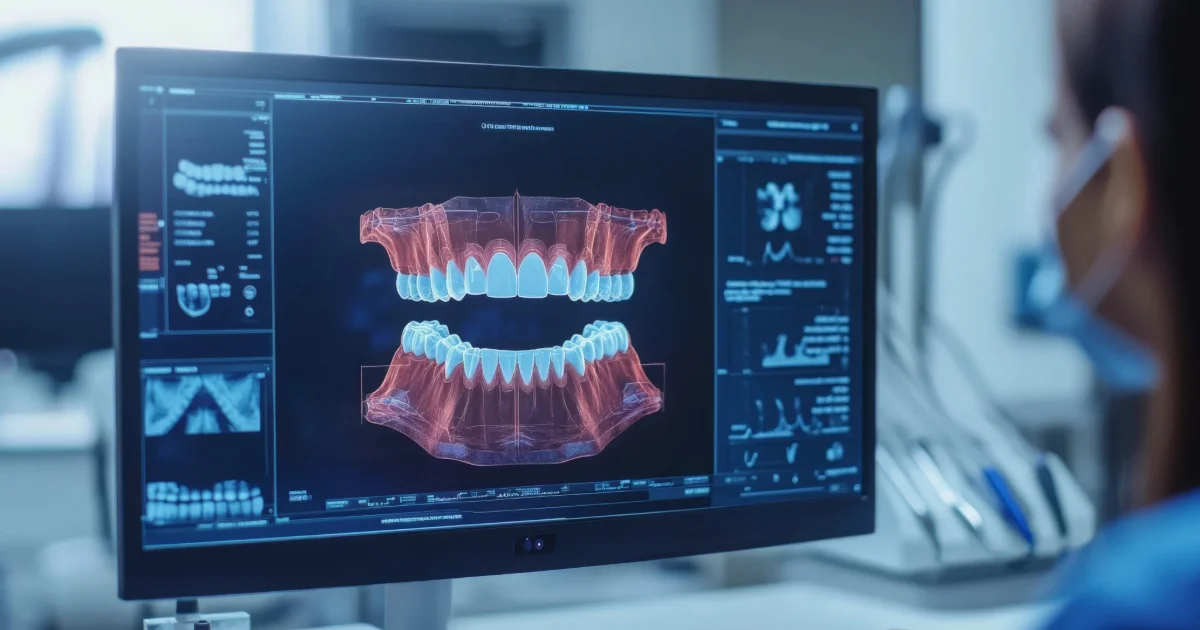

- In-house 3D imaging and digital scanning for precise planning.

All Michigan Implants stands out as the best dental implant clinic Detroit, thanks to our modern facility, patient-first approach, and consistently excellent results. Whether you’re a candidate for same-day All-on-4 implants or require a staged procedure, we’ll walk you through every step.

Visit our state-of-the-art dental implant center in Detroit, offering full-service implant care including consultations, imaging, surgery, and restorations—all under one roof.

Yes! Same-day All-on-4 implants are safe and effective when performed by an experienced provider using proper diagnostics and surgical planning.